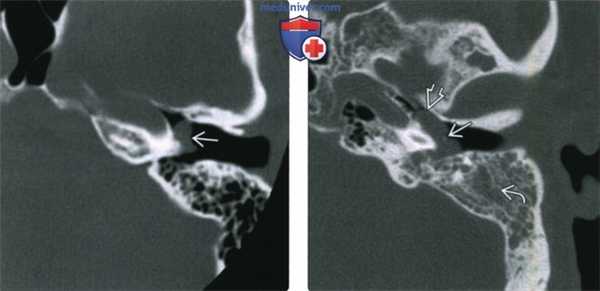

(Слева) При аксиальной КТ левой височной кости определяется дольчатое мягкотканное образование в нижних отделах мыса улитки, сопоставимое с ГТП.

(Справа) При КТ визуализируется крупное объемное образование в полости среднего уха. Опухоль приводит к выпячиванию барабанной перепонки кнаружи вокруг «пупка» (umbo) в области рукоятки молоточка. Обратите внимание на распространение в проксимальные отделы евстахиевой трубы и снижение пневматизации ячеек сосцевидного отростка из-за обструкции входа (адитус).

(Слева) При корональной КТ в коаном окне визуализируется маленькая ГТП, расположенная в нижних отделах мыса улитки, сразу же краниальнее и медиальнее барабанного кольца. На единавенном корональном изображении ГТП выглядит практически неотличимой от аберрантной внутренней сонной артерии (ВСА), однако в этом случае ниже улитки видна нормальная ВСА.

(Справа) При корональной МРТ Т1 ВИ С+ FS определяется ГТП в виде едва заметного фокуса накопления контраста снизу и снаружи от улитки. Без данных анамнеза рентгенолог легко может пропустить такую маленькую ГТП.